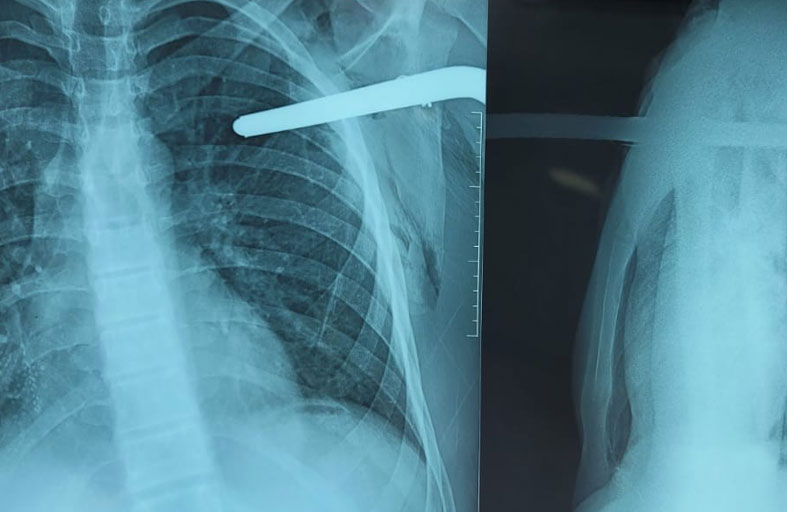

شهدت غرفة الطوارئ في مستشفى تركي مشاركة نادرة بين جراحين ورجال دفاع مدني؛ لإنقاذ مريض اخترق قضيب معدني طويل صدره من طرفين.

ووصل الرجل إلى المستشفى بإصابة خطيرة في موقع بناء بمحافظة "هاتاي" جنوبي تركيا، تسببت بدخول القضيب الحديدي من منطقة الصدر الأمامية وخروج طرفه الآخر من أعلى الخاصرة اليمنى.

وأظهر مقطع فيديو عمل عناصر الطوارئ الذين استخدموا منشاراً كهربائياً لقص الحديد بعد توفير جدار حماية لجسم المصاب. وجرت كل تلك العملية بينما المصاب مستيقظ ويشاهد عملية قص القضيب الحديدي، فيما يحاول الفريق الطبي طمأنته. وقالت وسائل إعلام محلية، إن عمل عناصر الدفاع المدني استغرق نصف ساعة تقريباً، قبل أن ينسحبوا ويتركوا باقي المهمة للفريق الطبي. وأضافت أن الرجل تحسنت حالته بعد أربعة أيام من الحادثة، ونجاح عملية إخراج القضيب الحديدي من صدره، ويتعافى في المستشفى استعداداً للمغادرة.